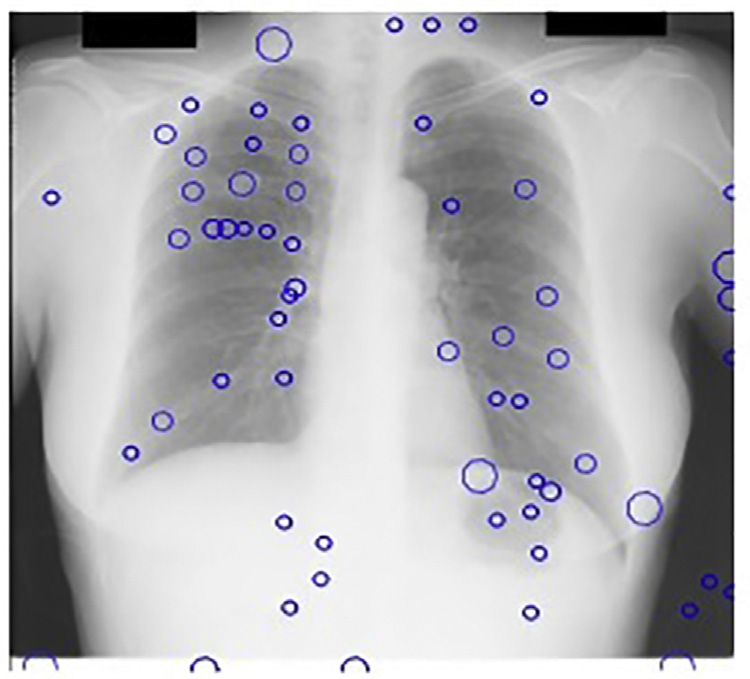

尽管胸部X光在临床日常中提供了重要的诊断检查,但由于相关诊断结构与无关的骨性结构重叠,使得影像较为复杂。因此,当前计算机辅助诊断系统(科皮尼、迪乔蒂、法尔基尼、维拉里和瓦利,2003年;吉格尔、土井、麦克马洪、梅茨和尹,1990年;德科宁等人,2013年;兰格、普拉特和因巴尔,1997年)在胸部X光片中面临的主要挑战是检测与肋骨、肋骨交叉及锁骨重叠的结节,如图14.1所示。这些骨性结构会导致大量的假阳性结果,正如凯瑟尔奇和吉田(2002年)所指出的

使用主成分分析滤波器进行肋骨抑制的结果如图14.2B所示。采用标准的高斯检测器高斯拉普拉斯掩模(LOG)来寻找可能存在结节的峰值区域。在原始胸部X光图像中应用该掩模导致了大量的假阳性,如图14.2A 所示,其中许多假阳性出现在肋骨上。

然而,在使用主成分分析滤波操作进行肋骨抑制后,该掩模除了检测到真正的结节外,仅产生了极少量的假阳性。人们认为,假阳性数量的减少主要归功于对肋骨的有效抑制。

斑点检测器以JSRT数据库的X光图像作为输入。我们的多尺度斑点检测系统每幅图像平均检测到218个结节。由于在此阶段遗漏的任何真阳性在后续阶段都无法恢复,因此在获取多尺度LOG滤波器输出中的局部最大值时设置了较低的阈值。图14.17显示了基本CAD方案中我们的斑点检测器的输出。